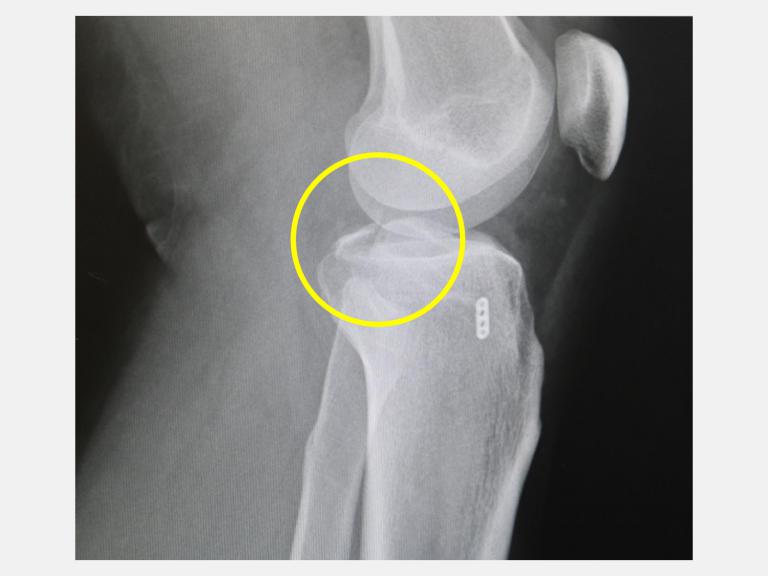

▲黃先生因車禍導致左腳膝蓋又腫又痛,檢查發現是脛骨後十字韌帶撕脫性骨折,仁愛長庚醫院運動醫學中心徐振恆醫師安排微創關節鏡輔助復位固定手術後,他隔天就開始下床走路,並進行復健運動,2個月之後已經回到正常生活。(圖╱仁愛長庚醫院提供)

台中一位28歲黃先生在騎機車上班途中發生車禍,左腳膝蓋又腫又痛,不只躺在地上爬不起來,甚至連膝蓋彎曲都有困難,由救護車送到仁愛長庚合作聯盟醫院(大里仁愛醫院)的急診室,X光檢查發現他左腳膝關節骨折,經進一步電腦斷層掃描後顯示是脛骨後十字韌帶撕脫性骨折(posterior cruciate ligament avulsion fracture)。運動醫學中心徐振恆醫師安排微創關節鏡輔助復位固定手術後,黃先生隔天就開始下床走路,並進行復健運動,2個月之後已經回到正常生活。